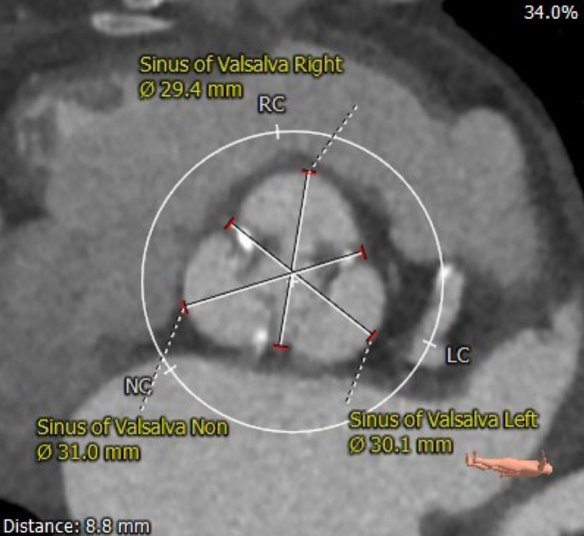

主动脉根部评估

CT 数据显示该患者为三叶式主动脉瓣